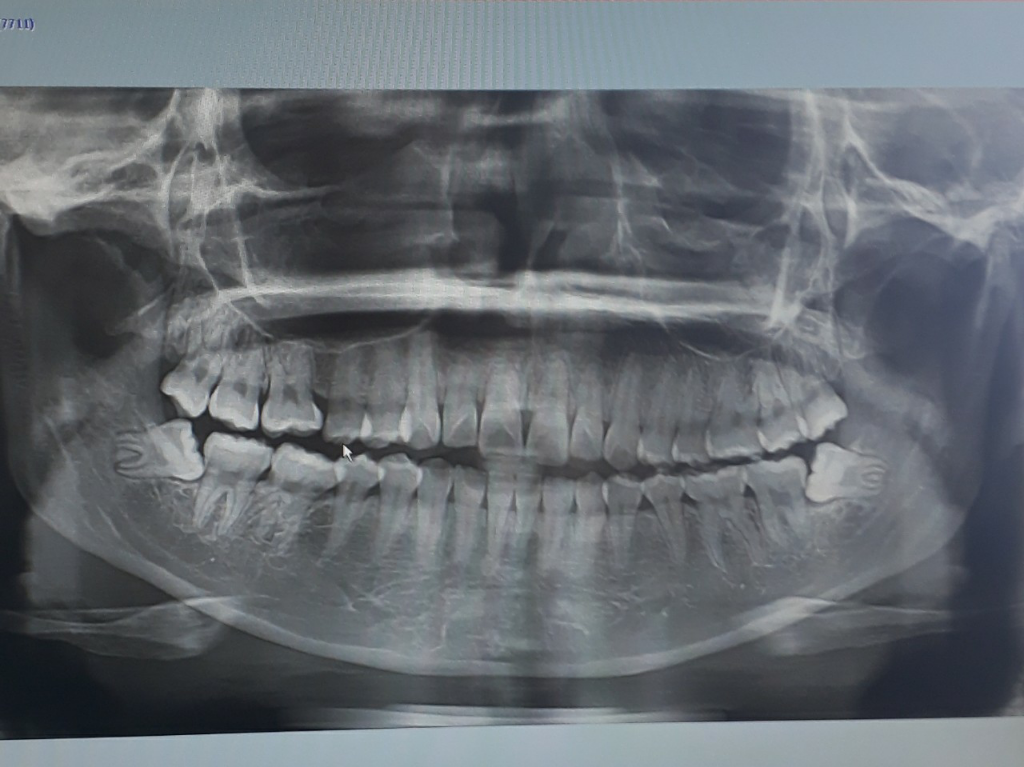

사랑니가 낳는데 양쪽다 거이 누워있어요 빼야될까요?

사랑니 아랫쪽에 두개가 누워있어요

일반 동네치과에서 뽑으면 마비가 온다해서 대학병원에 가야한다는데 빼는게 좋을까요? 그냥 평생 나두어도 될까요?

옆으로 누워있어서 주위 치아를 밀고 있는것 같습니다.